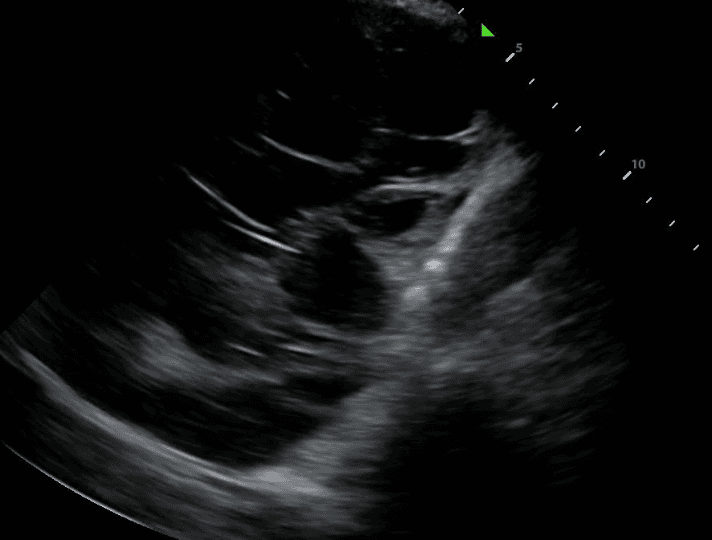

TB can lead to the accumulation of fluid in the pleural space, resulting in a pleural effusion. The incidence of these effusions range from 3% to 30% depending on the prevalence of TB and comorbidities such as HIV. On lung ultrasound, pleural effusion typically appears as anechoic (black) or hypoechoic (dark) fluid collection between the lung and the chest wall. The presence of pleural effusion in TB may indicate complications such as pleural TB or concurrent bacterial infection.